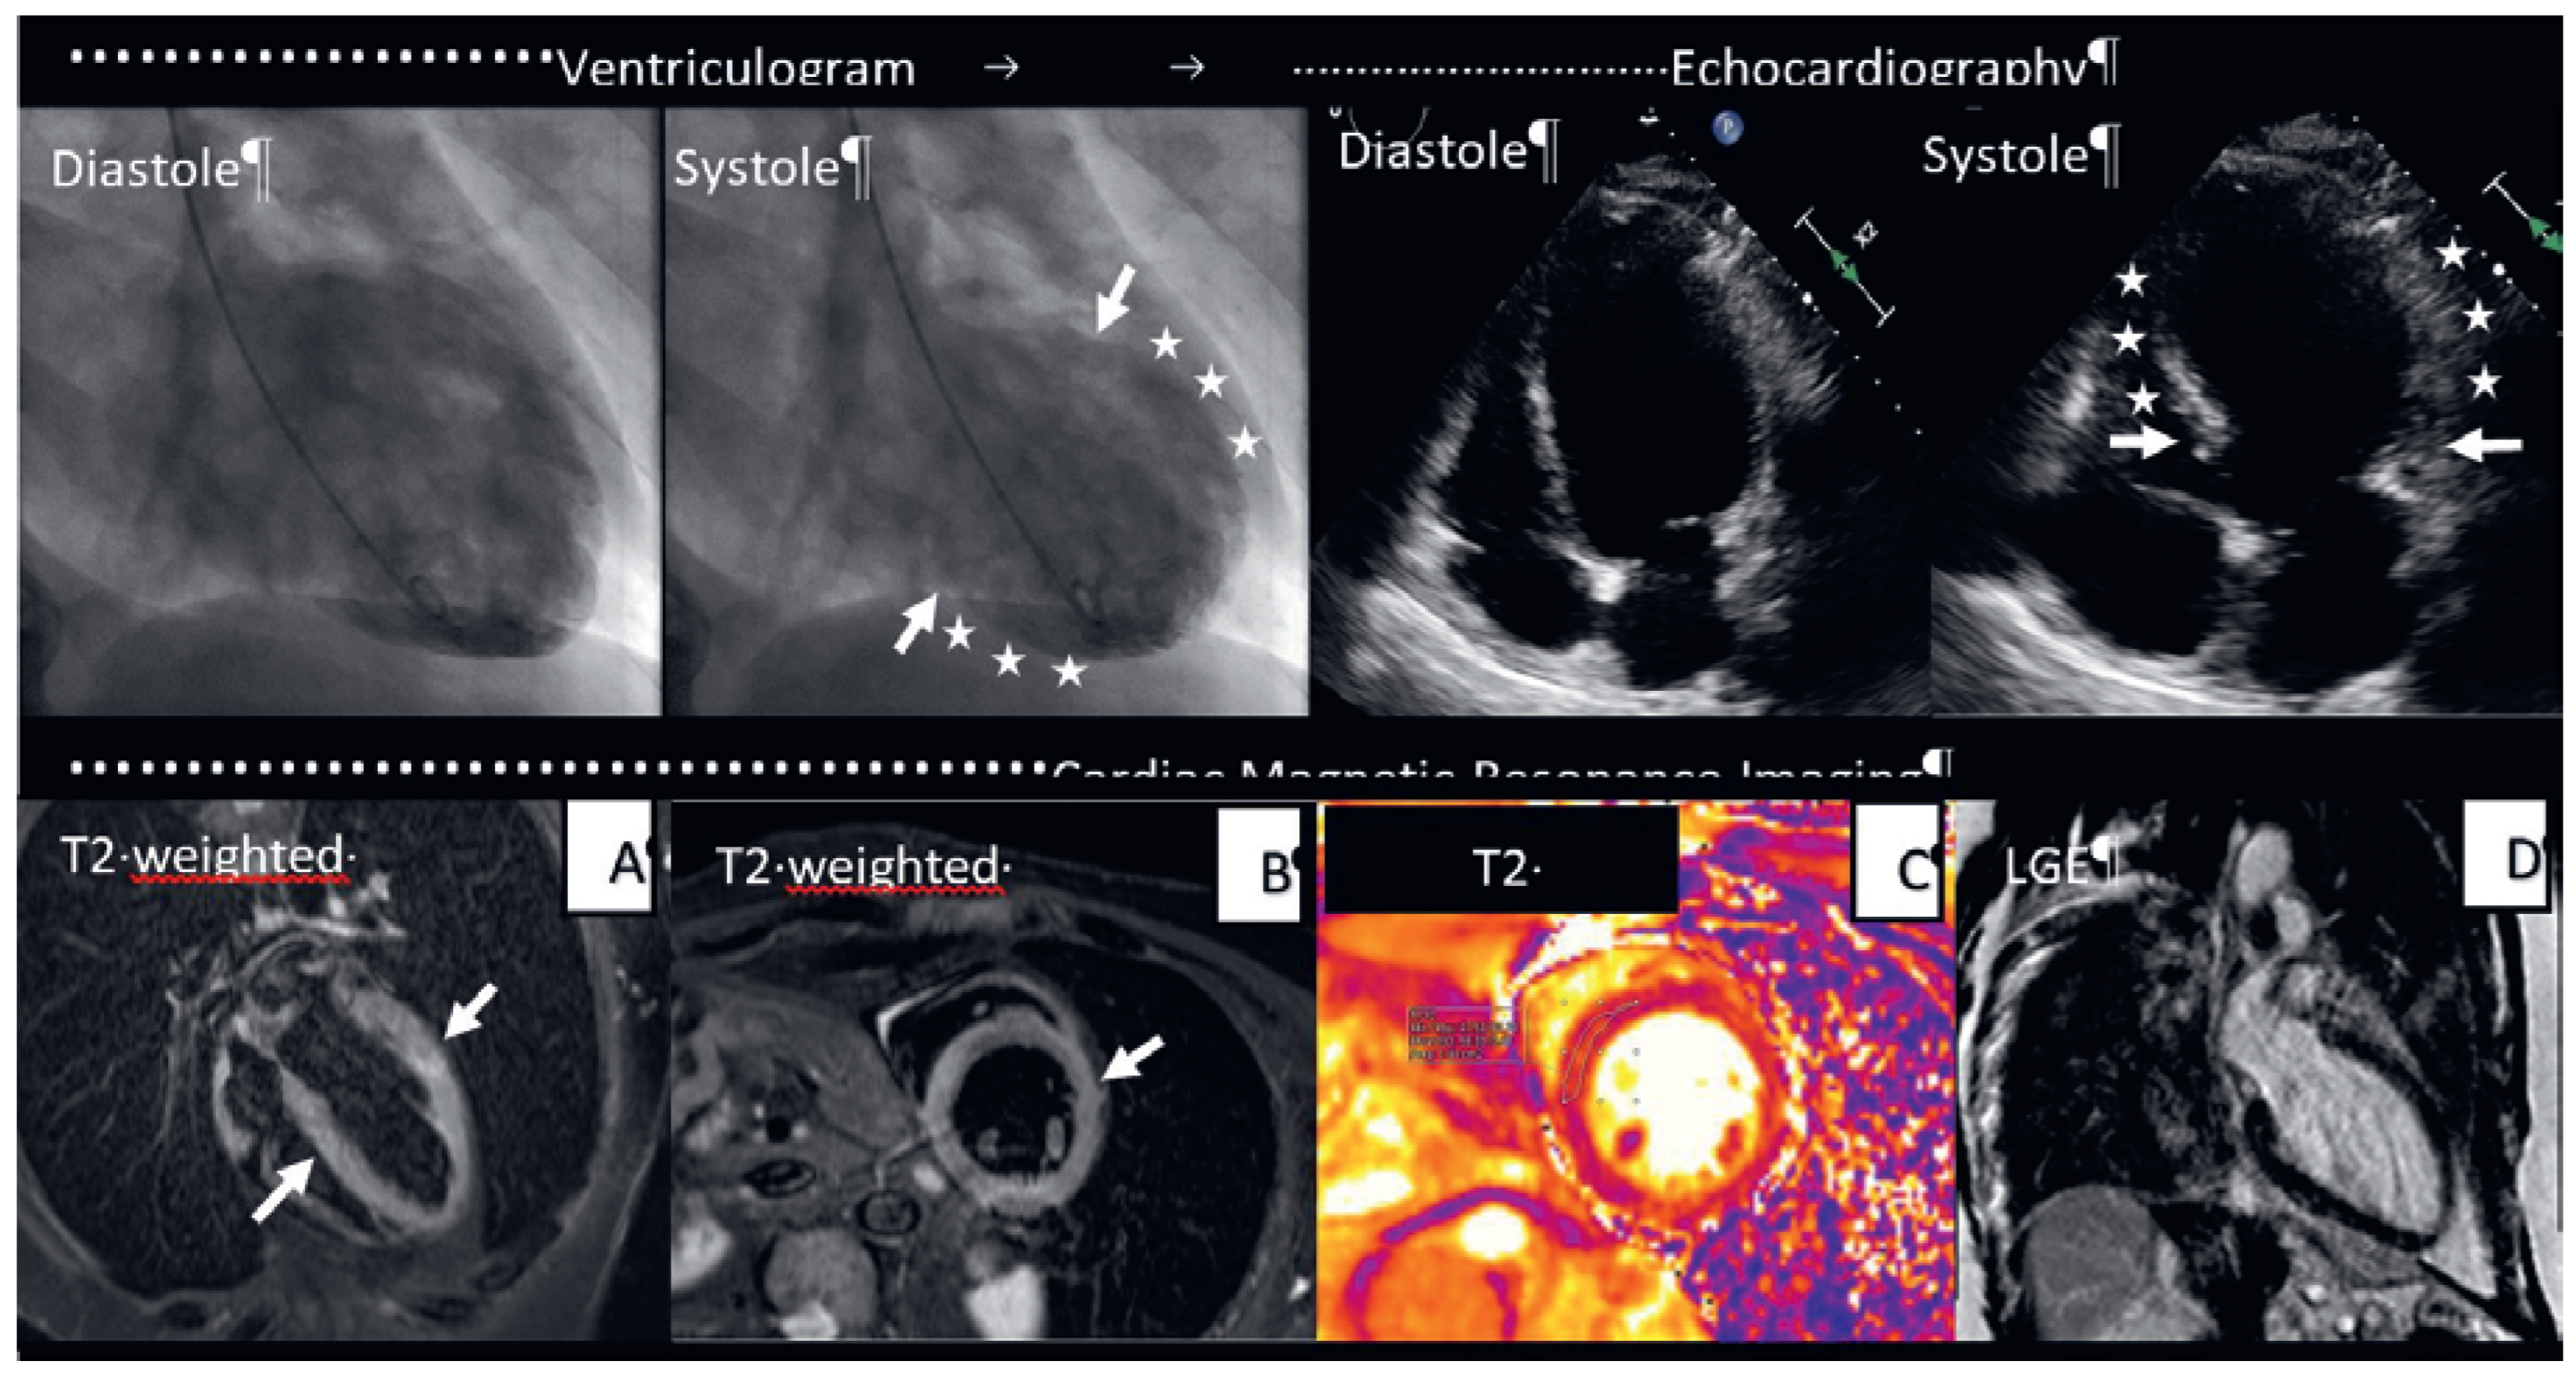

A 68-year-old female patient with history of arterial hypertension, renal failure KDIGO grade 3a and urothelial carcinoma was admitted to the emergency room with chest pain and high blood pressure (195/86 mm Hg). She was taking olmesartan and nebivolol. The symptoms started 7 days after receiving the second dose of mRNA-BNT162b2 (Pfizer/Biontech) COVID-19 vaccine. A retronasal severe acute respiratory syndrome coronavirus 2 polymerase chain reaction test was negative. Her high-sensitive troponin was elevated at a peak of 107 ng/l (reference < 14 ng/l) with a normal creatine kinase and slightly elevated creatinine at 88 µmol/l (reference interval 44–80 µmol/l). Creactive protein and leucocytes were within the normal range. The ECG showed ST depression over the anterior leads (V3–V5). We decided on an invasive strategy. Her Grace score was 99 points. Invasive coronary angiography ruled out coronary artery disease, but the ventriculogram showed mid-ventricular ballooning with preserved basal contraction and a mildly reduced left ventricular ejection fraction of 45%. Midventricular ballooning was confirmed by echocardiography and cardiac magnetic resonance imaging (CMR). CMR tissue characterisation further depicted extensive oedema in the mid-ventricular segments without evidence of myocardial infarction. There was no late gadolinium enhancement suggesting peri-/myocarditis and no pleural or pericadial effusion (Figure 1). As there were no other stressors that could be determined to be underlying the midventricular oedema and ballooning, the most probable diagnosis of COVID-19 vaccineinduced takotsubo syndrome was made. There were not any other triggers for takotsubo syndrome as physical or emotional stress, which could have increased the cardiosympathetic system.

Figure 1. Multimodality imaging using ventriculography, echocardiography and cardiac magnetic resonance of Takotsubo syndrome after COVID-19 vaccination with Pfizer/Biontech. CMR: (A,B) T2w imaging 4CH and SA: myocardial hypersignal suggestive of diffuse myocardial oedema at the midventricular segments (white arrows). (C) T2-mapping SA: raised T2 values at midventricular segments indicating oedema in these segments. (D) LGE 4CH: no evidence of myocardial infarction after the contrast administration.